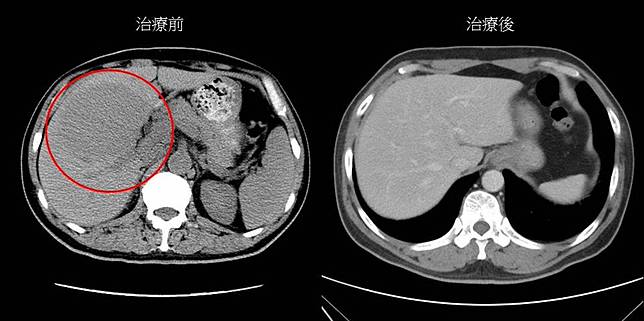

▲目前高精準性的放射治療及化學治療,副作用減輕,且有穩固的療效。(照/大林慈濟醫院提供)

出現反胃、嘔吐的症狀,57歲的翁先生3年前因為出現這些一般人眼中的「小症狀」就醫,沒想到檢查卻赫然發現肝臟已有一顆7公分大小的腫瘤,確診為小細胞B淋巴瘤,且在進行化學治療之後,肝腫瘤反而變大為9公分,最後在醫師建議下,使用立體定位放射治療後,腫瘤才完全消失。

大林慈濟醫院放射腫瘤科醫師林宏益指出,翁先生接受化療後,肝腫瘤反而由7公分增大至9公分,屬於對化療頑固性的淋巴瘤,醫療團隊建議他採用高精準度的身體型立體定位放射治療合併使用腫瘤內部同步劑量調整,治療才終於見效。

幸運的是,翁先生在治療過程中就可以看到肝腫瘤有輕微縮小,且只有輕微的疲累感及食欲不振,沒有出現嚴重的副作用,治療半年後追蹤時,肝腫瘤已完全消失,持續追蹤2年,也沒有肝腫瘤復發及明顯晚期副作用,如腸阻塞或慢性肝損傷等。